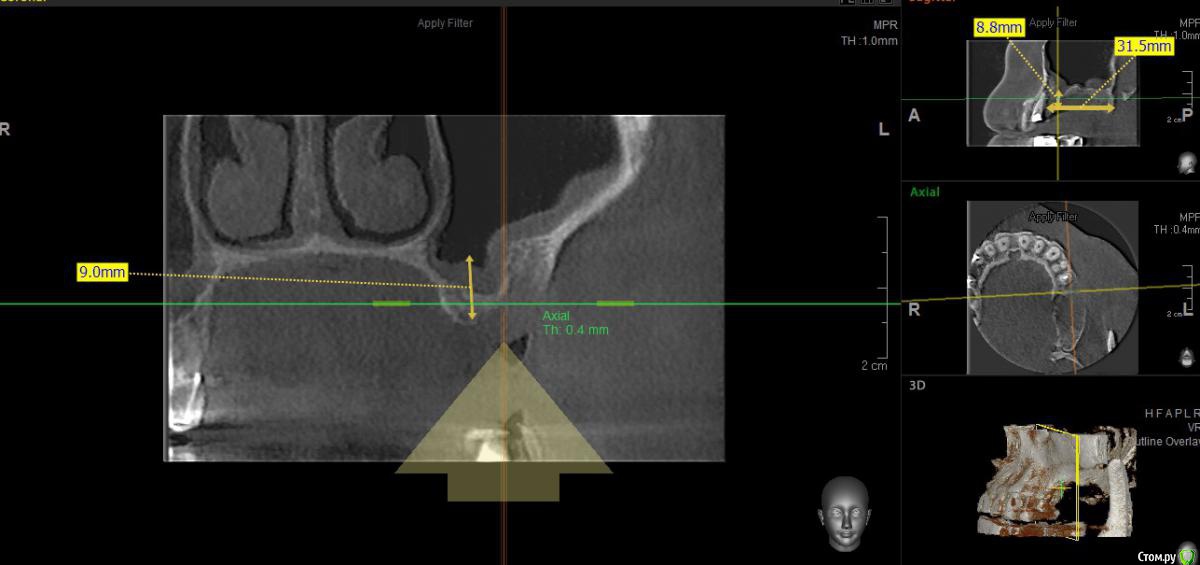

togrul Опубликовано 20 июня, 2017 Поделиться Опубликовано 20 июня, 2017 Добрый день коллеги. Необходима ваша помощь в понимании данной ситуации. обратился пациент на консультацию по поводу имплантации во 2 сегменте. При анализе кт обнаружил вертикальный дефект костной ткани. Вариант восстановления: 1 Восстановление высотытитановой сеткой2 Синус + установка 2х имплантатов Вопросы : как создать доступ для синуса при такой толстой кортикалке + сосуд проходит + анатомия стенки и нужно ли работать в высоту Спасибо заранее Ссылка на комментарий